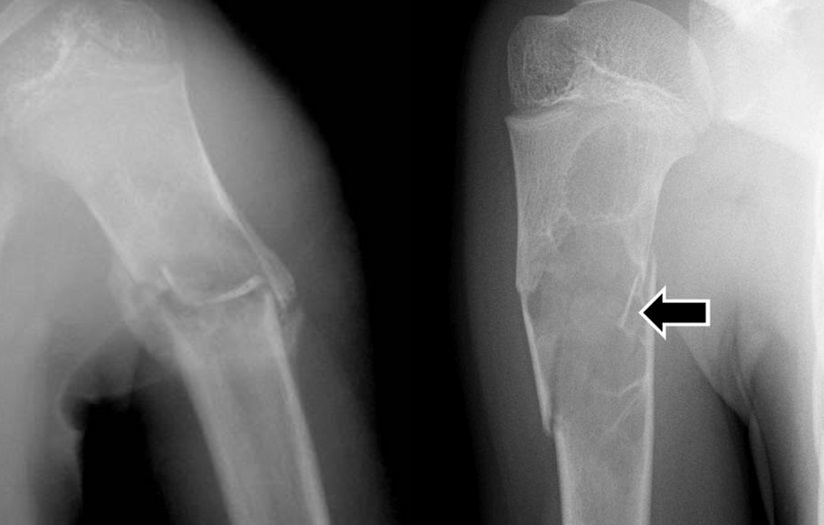

14

Q

Qual o diagnóstico?

A

Lesâo lítica, diafisária, central

Osso imaturo

dx: COS

* ** acomete metáfise e diáfise central

How well did you know this?

1

Not at all

2

3

4

5

Perfectly